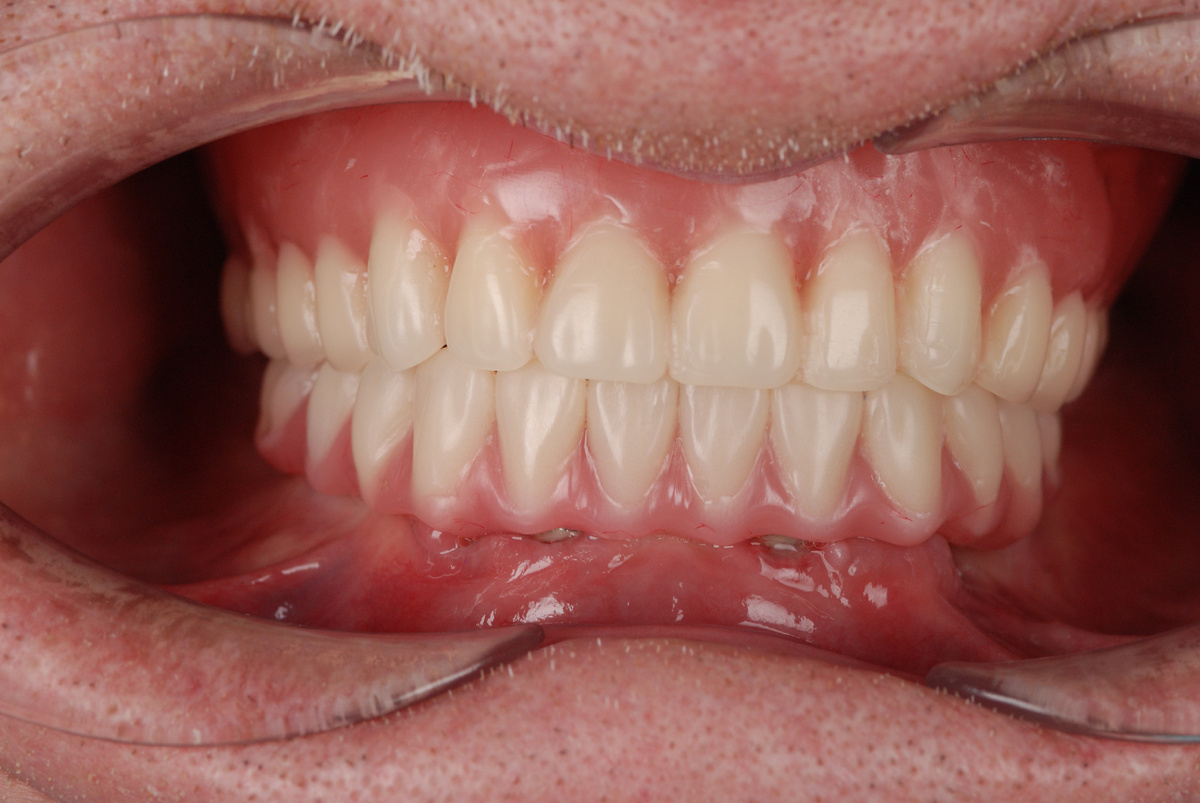

Нашему пациенту 87 лет. Сейчас он с временным протезом из пластмассы, под ним приживаются импланты и восстанавливается десна. Через 3 месяца временную конструкцию сменят постоянные зубные дуги.

Я не стал ждать финальной точки и поспешил показать вам этот отрезок нашего пути. Мне не терпелось сообщить, что нет возраста, когда человек может полностью и безоговорочно смириться с утратой зубов, невозможностью нормально есть и хорошо выглядеть.

Нижняя треть лица не сопоставима в формате ДО-ПОСЛЕ, потому что архитектура полностью поменялась. Вернулась опора для тканей в виде зубов, губы больше не проваливаются, подбородок перестал стремиться к носу.

С одной стороны, снимать протез на ночь - обязательно условие, с другой - возрастные эстетические проблемы усугубляются, когда ткани лица находятся без привычного каркаса. Понятно, что для мужчины в возрасте нашего пациента в этом драмы нет, но полное отсутствие зубов приключается и с женщинами активного возраста. И эта информация больше для них, безусловно. Зубы - основа молодости лица. И что немаловажно - зубы адекватной высоты.